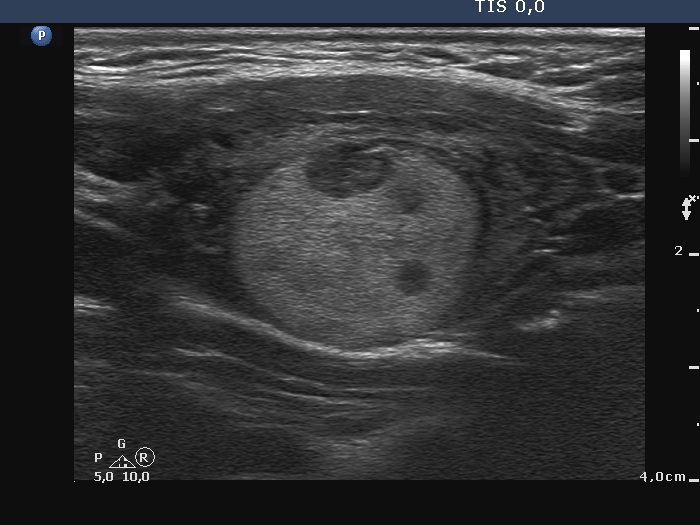

Third examination - seven years after the first examination (third row of images)

Clinical presentation: The patient hasn't been operated on, yet. She came to a repeat examination because of neck complaints, she felt pressure when lying down.

Palpation: a firm nodule in the left lobe.

Laboratory tests: TSH 1.70 mIU/L.

The dimensions of the nodule in the left lobe were 41x25x50 mm, width, depth, length, respectively, the volume of the lesion was 26.8 mL.

FNA resulted in follicular tumor.

Histopathology disclosed minimally invasive follicular cancer. The largest diameter was measured 55 mm. Both capsular and vascular invasions were found microscopically.

Comments. It is worth highlighting three changes. First, the nodule echogenicity has changed over time - from clearly hyperechoic to moderately hypoechoic. Secondly, the nodule substantially increased in size. This is the cause for the disappearance of the halo, due to the nodule growth, the capsule became invisible thin. Thirdly, the pattern of the intranodular hypoechoic parts has also changed.